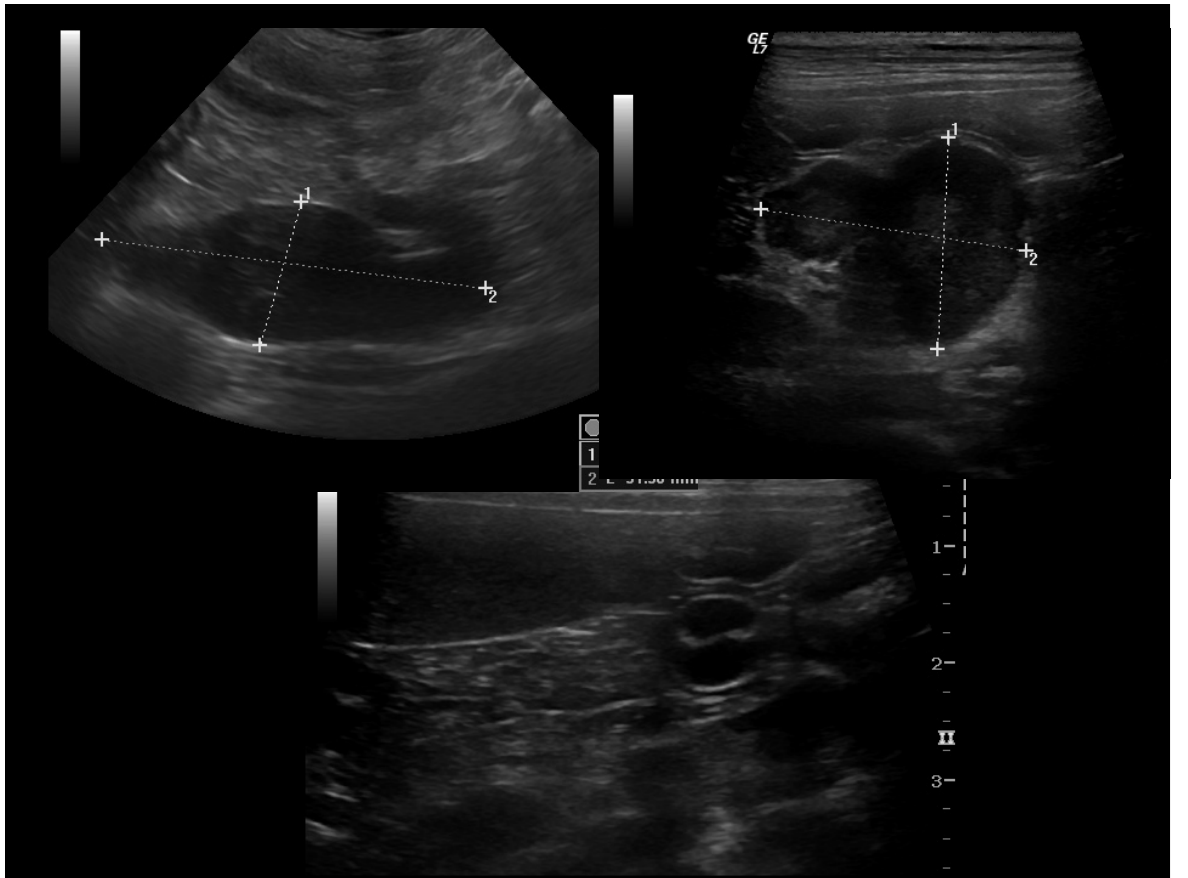

Diagnostic Imaging: Ultrasound

Parenchymatous organs • Occasional classical “ocelot’s pelt” lesions esp spleen – Appearance can be very variable • Guidance for FNAs/tru-cut biopsies – Cranial mediastinal – Renal • Useful for imaging gut: layering • Mesenteric and hepatic lymph nodes • Remember there are many possible causes of mesenteric lymphadenopathy

moniter remission

what is this

enlarged LN

hypochoeic, v heterogenouss